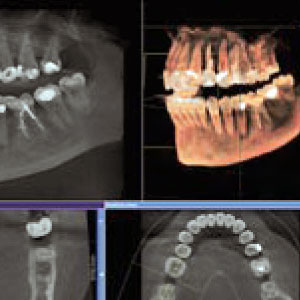

Our McDonough dental practice is equipped with cone beam CBCT diagnostic radiography to support our dentists in evaluating the overall health of the jaw joints, teeth and facial structures. This 3D imaging technology provides multiple views of the bone and soft tissue to share findings with our patients and to assist with treatment recommendations.